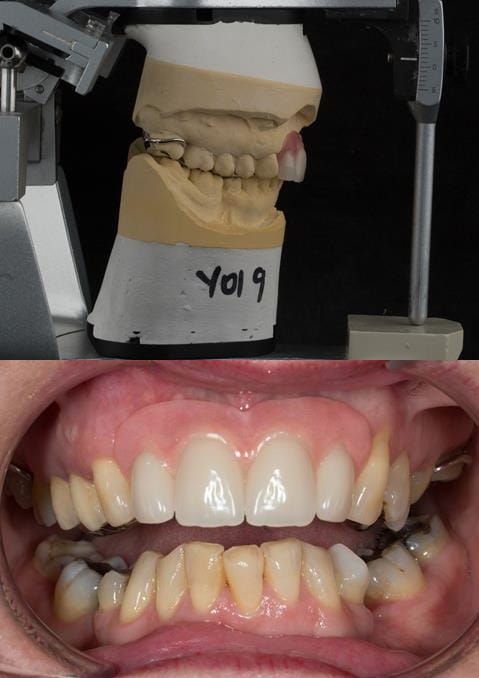

Provision of a maxillary cobalt chromium based partial denture/protective occlusal splint in a heavily restored dentition

- Extract the upper 2-2 teeth and replace with an interim acrylic based partial denture. Reline the interim denture over 9 - 12 months, replacing with a definitive cobalt chromium based partial denture. The definitive denture would ideally be designed as an occlusal protective splint to reduce the the potential for mechanical wear and breakages of the moderately/heavily restored maxillary dentition. In addition, should further upper teeth require extraction they could be added on to the denture cobalt chromium framework - therefore a new prosthesis would not be required as future teeth are lost. This option would produce an excellent aesthetic outcome. This is the option the patient chose to have.

Following consultation and second discussion appointment the patient chose to have option 3 namely, a maxillary cobalt chromium based partial denture/protective occlusal splint. The clinical situation and treatment process is shown in detail below with photographs. The patient was successfully rehabilitated with this and her quality of life considerably improved. The clinical work was provided by Finlay and the technical work by Rowan.